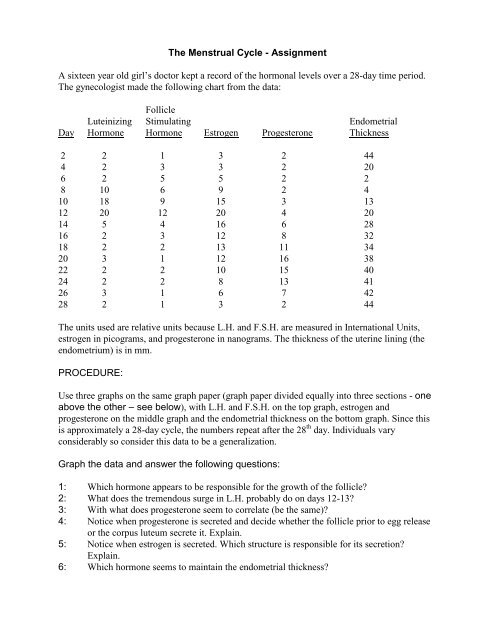

The Menstrual Cycle Assignment A Sixteen Year Old Girls .

Menstrual Cycle Graphing .